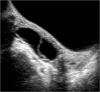

We present a case of a 14-year-old girl, Bacillus Calmette-Guérin (BCG) vaccinated, who presented with vague symptoms of abdominal pain, weight loss, and fatigue. Imaging studies revealed a pelvic mass, later found to be pelvic tuberculosis, a rare diagnosis to consider at this age. The diagnostic approach was difficult, since all investigations pointed strongly to a malignancy, from clinical, imaging (ultrasound and magnetic resonance), laboratory (elevated CA-125), and even macroscopic findings at laparotomy. Histopathology was the first hint (noncaseous granulomata), but the ultimate documentation of Mycobacterium tuberculosis relied on a persistent clinical suspicion, despite contradicting results. Surgical approach could have been mutilating, with irreversible consequences, considering it was a girl with a long reproductive life ahead. Tuberculosis is still a great masquerade, especially the extrapulmonary forms, and although infrequently seen at this age, it should thus be considered in the differential diagnosis of complex pelvic masses in order to avoid surgical iatrogeny/morbidity.